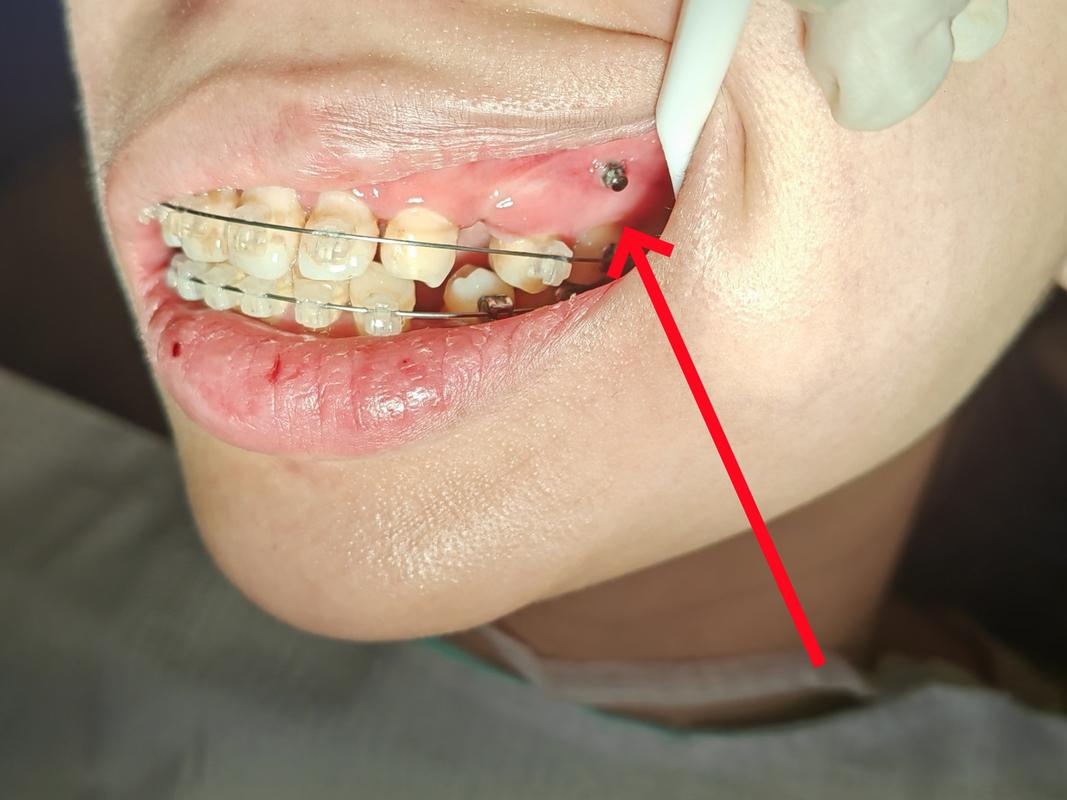

- 植入种植体:用专用植入器在预定位置钻孔(骨量充足时可直接植入),将直径1.5-2.0mm、长度6-12mm的钛合金种植体旋入牙槽骨,顶部留出1-2mm于口腔黏膜下方,便于后续加力。